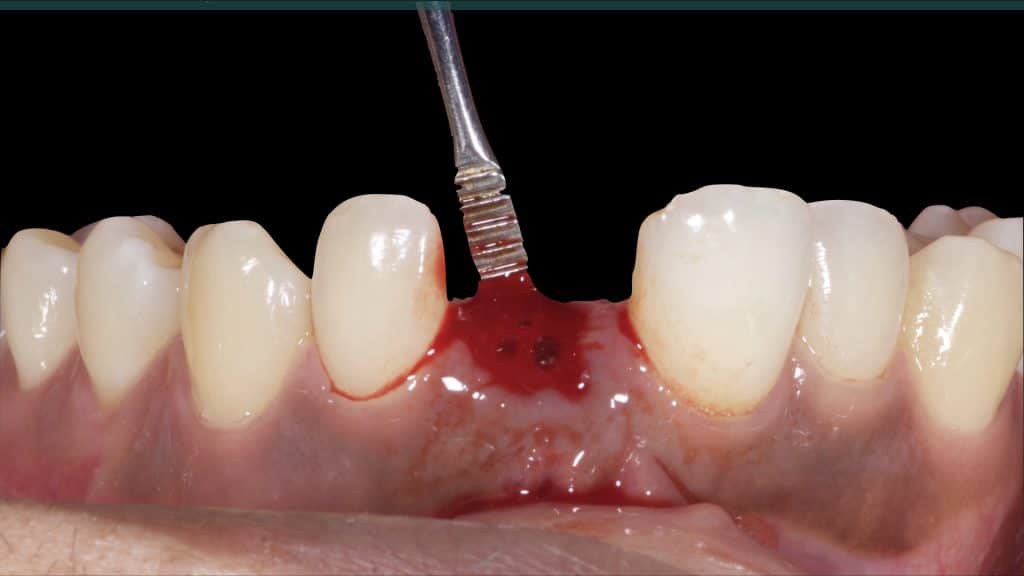

Occlusal check